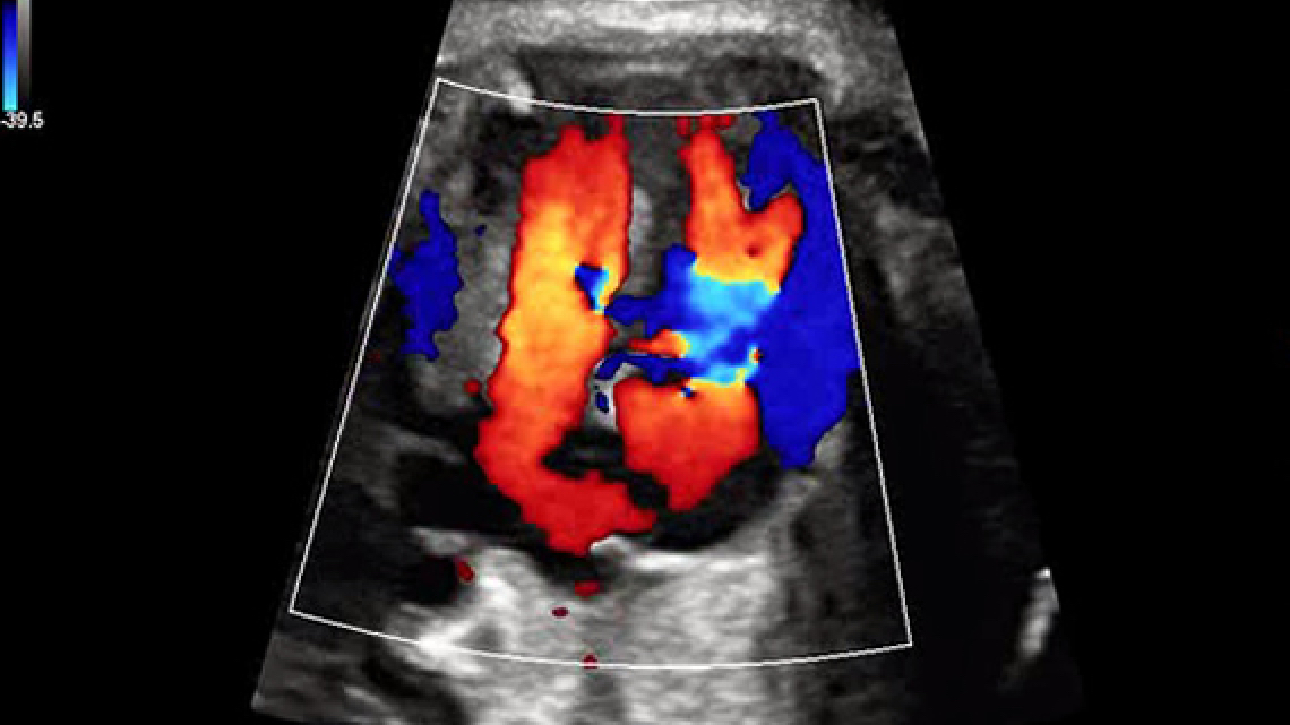

Imagens clĂnicas